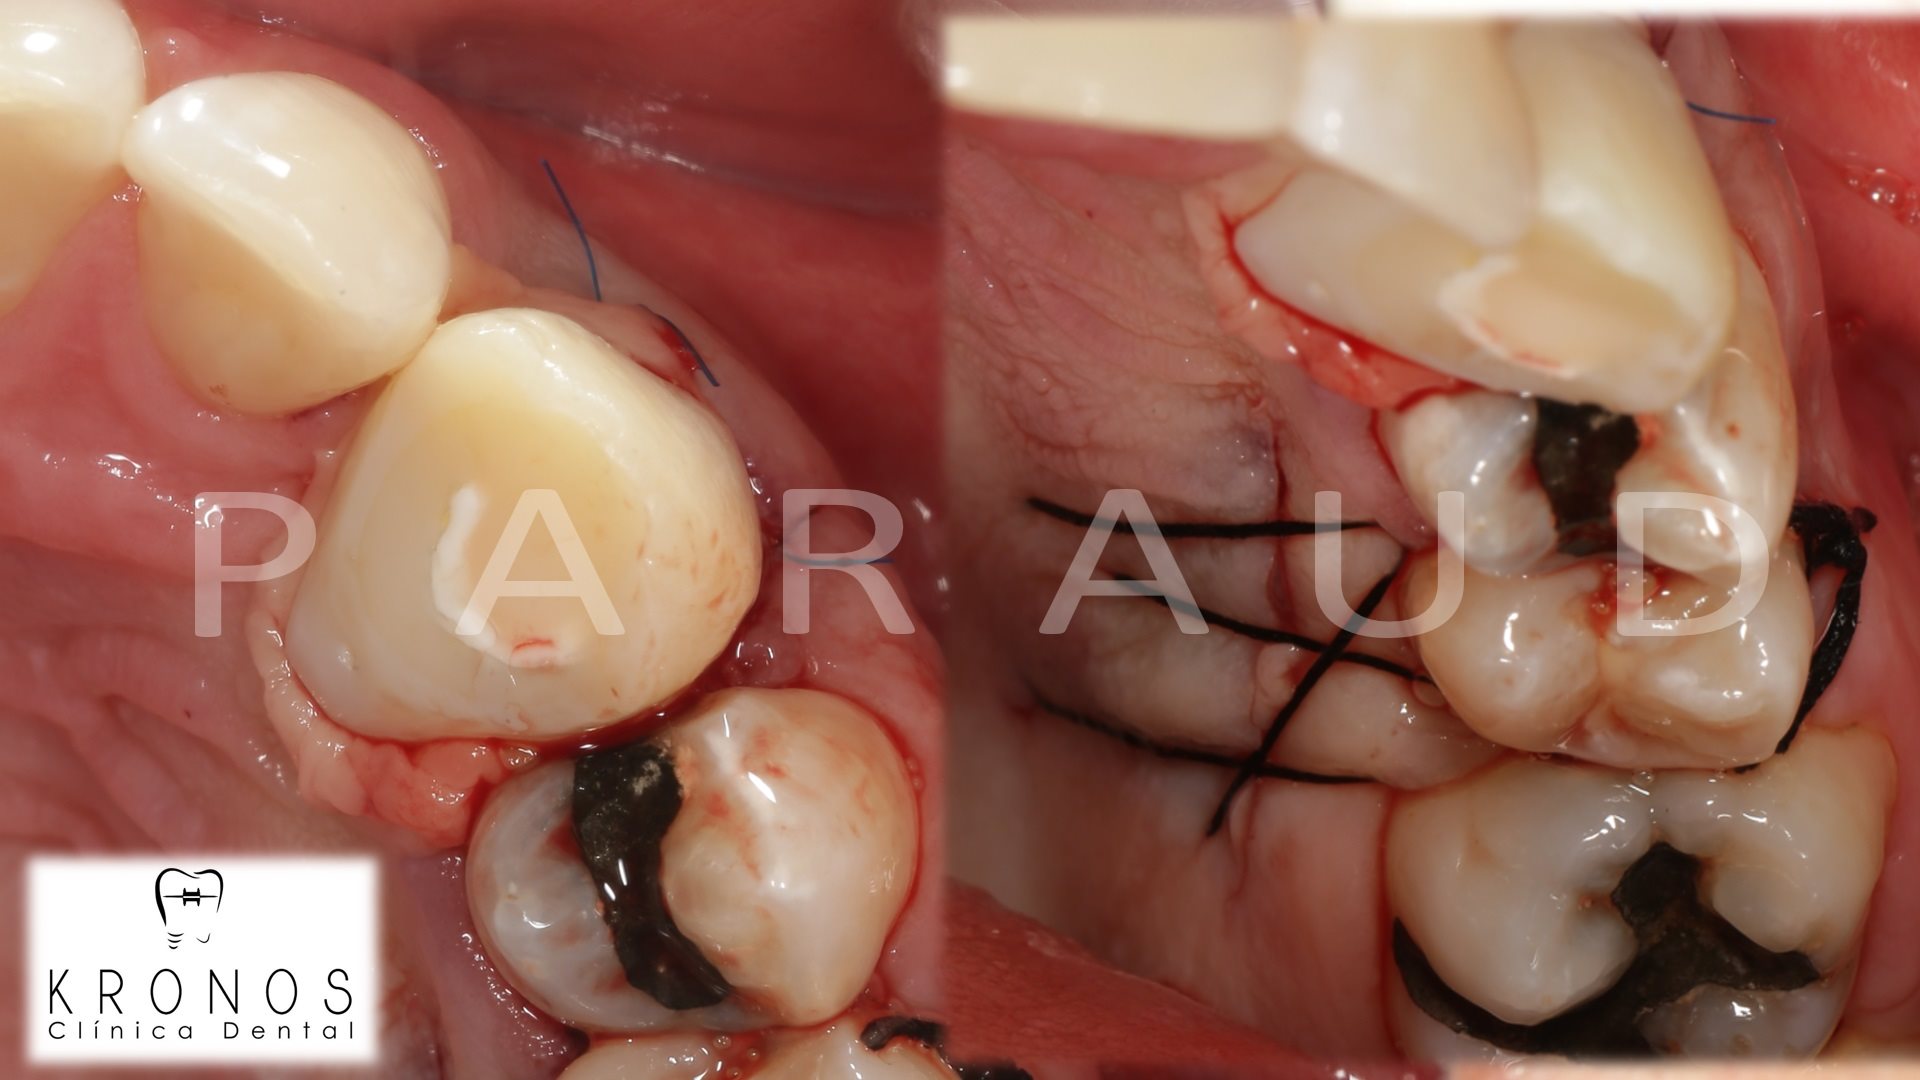

Clinical case: AnyRidge immediate loading

- Courtesy of Dr. Andres Paraud Freixas, Chile -

AnyRidge, ISQ value, initial stability, immediate loading, KnifeThread, maxillary anterior, Mega ISQ, Dr. Andres Paraud Freixas

AnyRidge implant system, Mega ISQ, Digital prosthesis